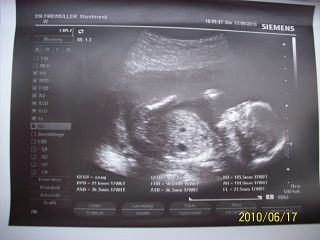

Csajok tegnap nagyon szuper napom volt, megvolt az UH, szerencsére minden rendben Gombóckával, nagyon cukin mocorgott,sajnos nem mutatta meg mi van a lába között, doki bácsi azt mondta, hogy biztosat nem tud mondani, tippelni meg nem szeretne, így 3 hét múlva kell mennem legközelebb, genetikai Uh-ra ( képzeljétek itt nincs benne a rendes protokollban a genetikai UH, úgyhogy 80 euróért mehetek a Welsi kórházba megcsináltatni)!!Amúgy doki bácsi tök kedves volt....Ezért baromira haboztam, hogy megint felhozzam ezt az otthon maradást....És képzeljétek, hogy megkaptam a zöld utat a tiszti orvoshoz, ráadásul azt írta a papíromra, hogy meg van rövidülve a méhnyak és koraszülés veszélye áll fennt, azaz veszélyeztetett terhes vagyok persze ebből egy szó sem igaz, na de ilyen indokkal a tiszti orvos elmehet a náthás francba, erre nem fog tudni mit mondani :D :D Azaz ha minden jól megy, többet nem kell mennem dolgozni a szülésig, juhéééééééj :lol: :lol: :lol: Annyira boldog vagyok, hogy azt nem is tudom elmondani, szép az élet :D

Ja és egy kép a szépségemről: